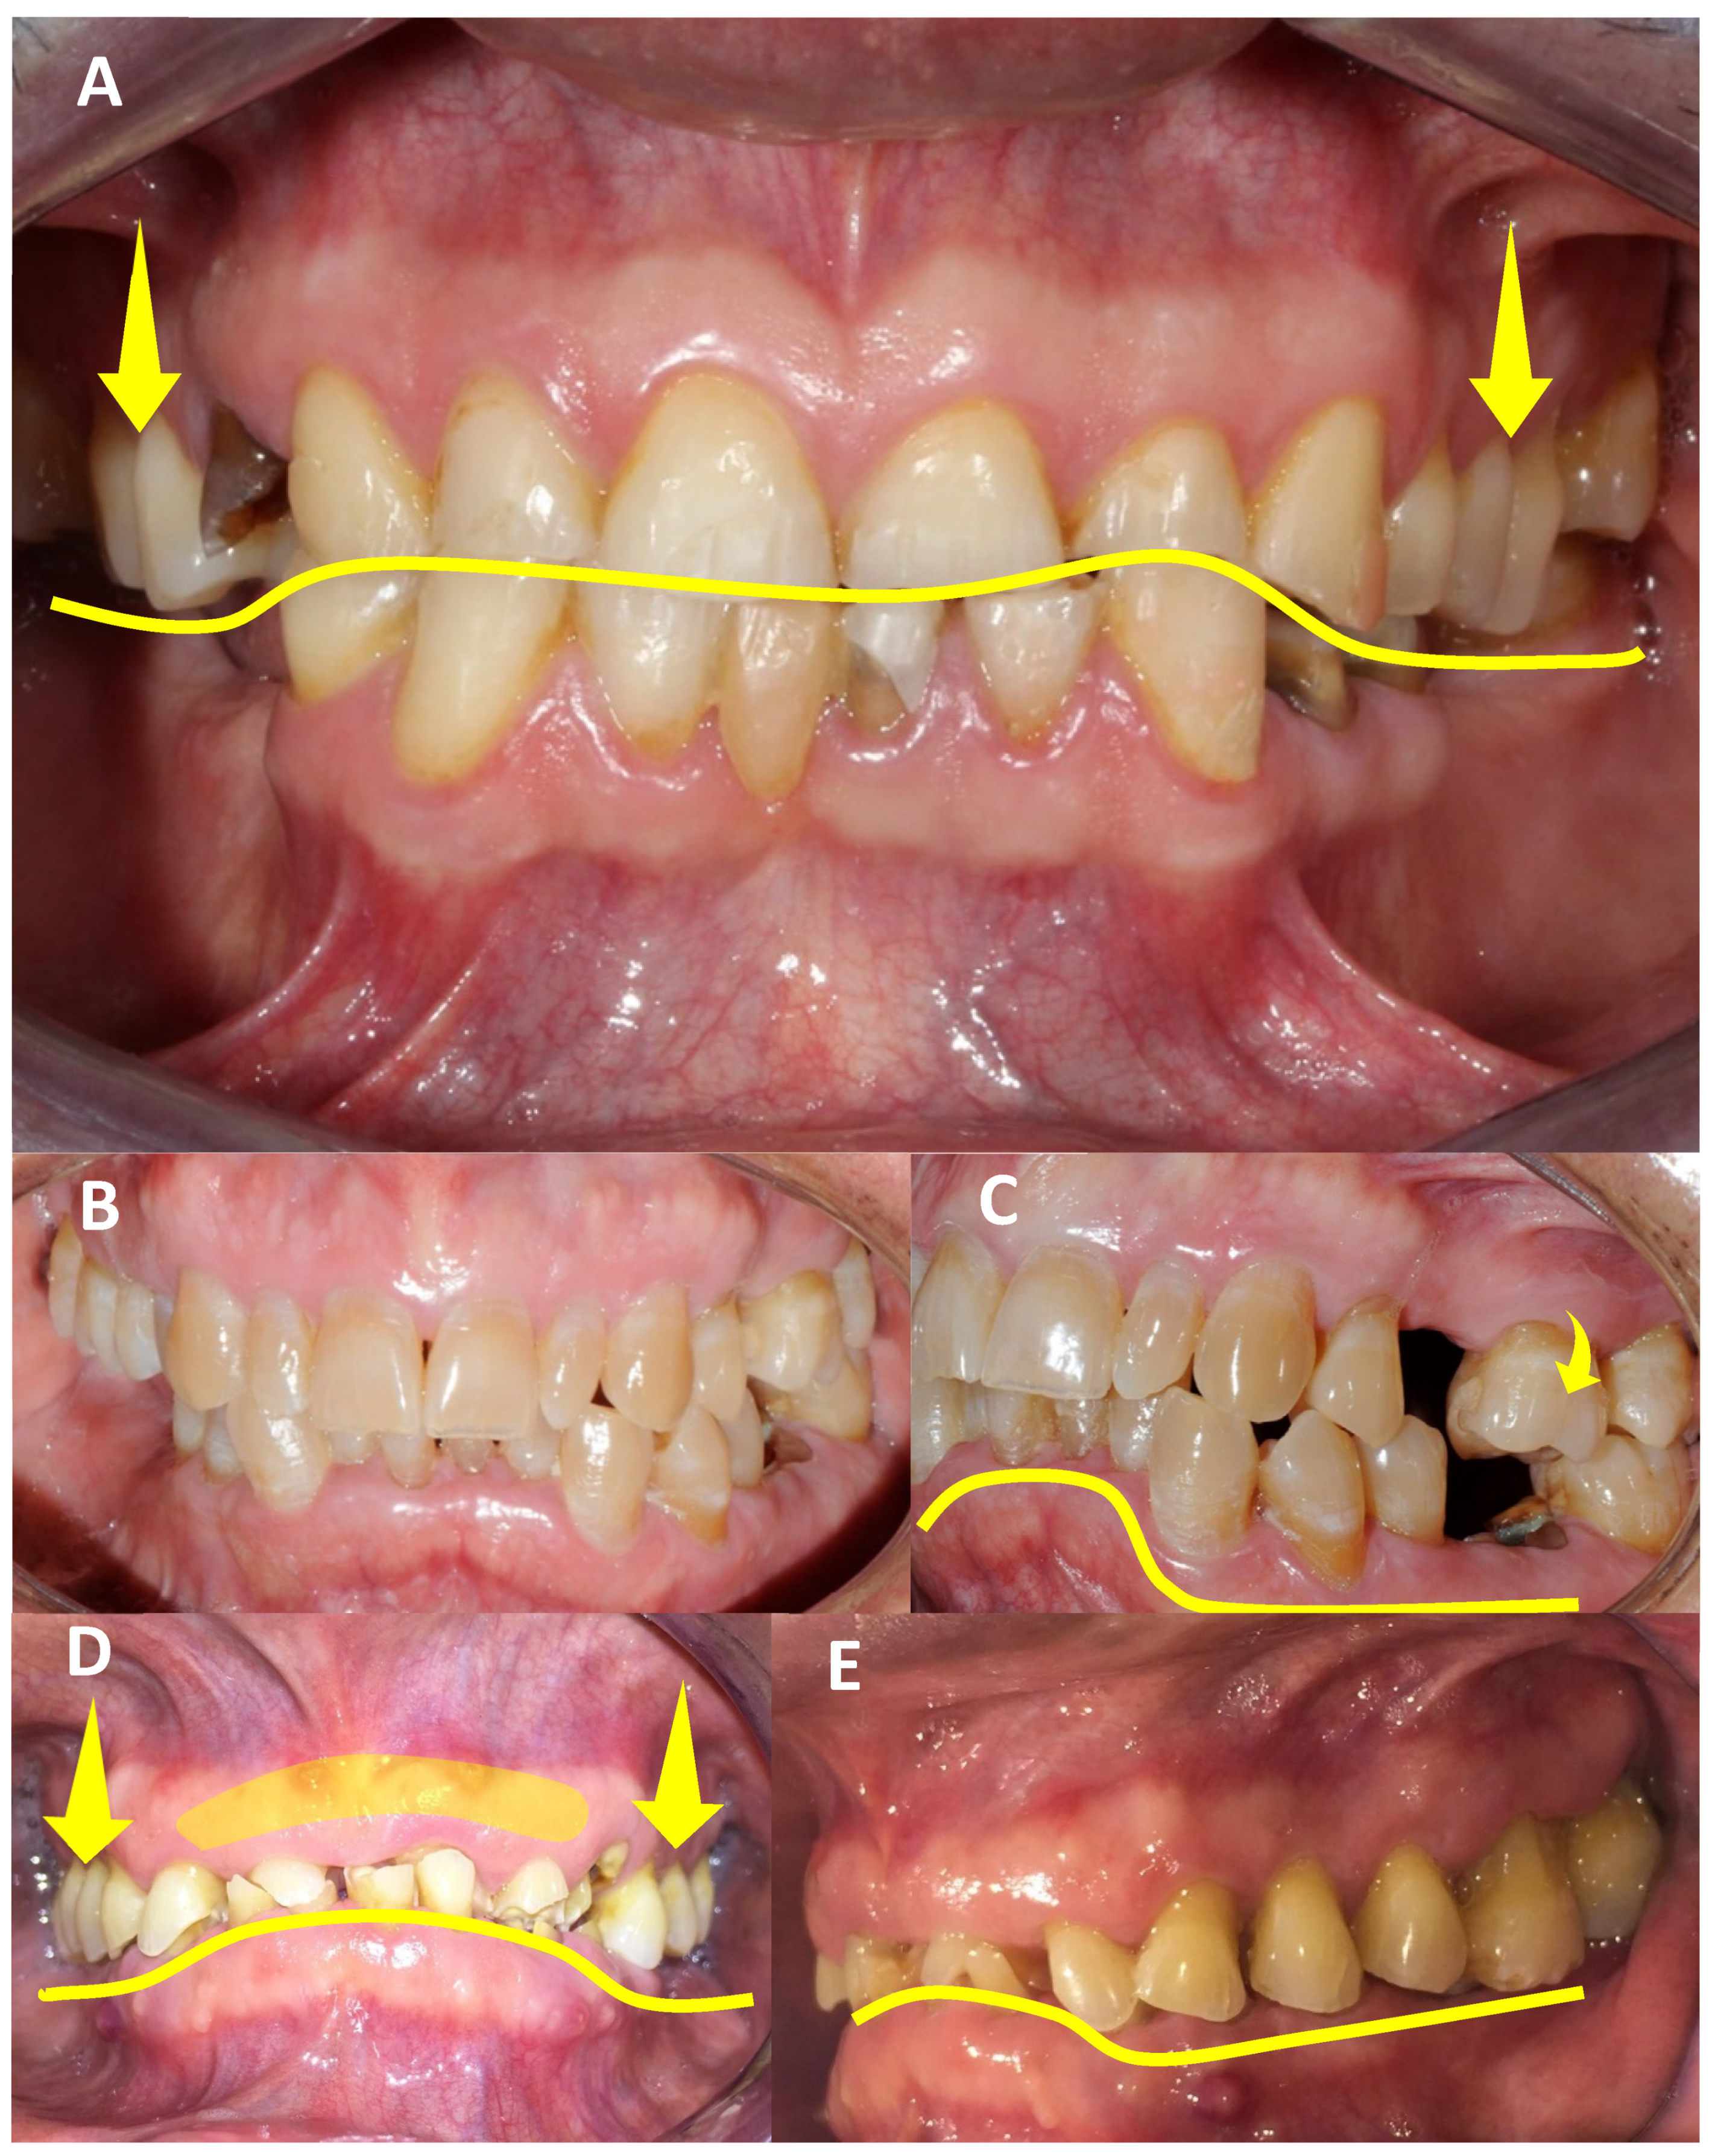

3.3.4. Dental-Level Influences